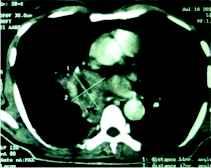

After 10 days of treatment, patient's diabetes was controlled but high grade fever and dyspnoea persisted. CT thorax was done which revealed necrotic soft tissue mediastinal mass measuring 5.1×4.7 cm in the right parahilar location (figure 1) closely encasing the bronchus intermedius and right inferior pulmonary vein. Few necrotic nodes abutting the primary mass lesion were also noted. Fiberoptic bronchoscopy revealed obstruction of right main bronchus with soft tissue with mucosal hyperemia. The material aspirated through trans-bronchial needle aspiration displayed non-septate fungal hyphae suggestive of zygomycosis on smear examination (figure 2).

Figure 1: Coronal section of CT thorax (mediastinal window) shows a big mass (5.1×4.7 cm) in right parahilar mediastinum. The outline of the mass is fairly regular with occasional spiky projections and an area of liquefaction (necrosis) is seen within at the center.